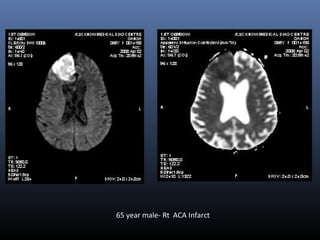

65 year male- Rt ACA Infarct

Evaluation of acute stroke on DWI

 The DWI and ADC maps show changes in ischemic brain within

minutes to few hours

 The signal intensity of acute stroke on DW images increase

during the first week after symptom onset and decrease

thereafter, but signal remains hyper intense for a long period

(up to 72 days in the study by Lausberg et al)

 The ADC values decline rapidly after the onset of ischemia and

subsequently increase from dark to bright 7-10 days later .

 This property may be used to differentiate the lesion older than

10 days from more acute ones (Fig 2).

 Chronic infarcts are characterized by elevated diffusion and

appear hypo, iso or hyper intense on DW images and

hyperintense on ADC maps